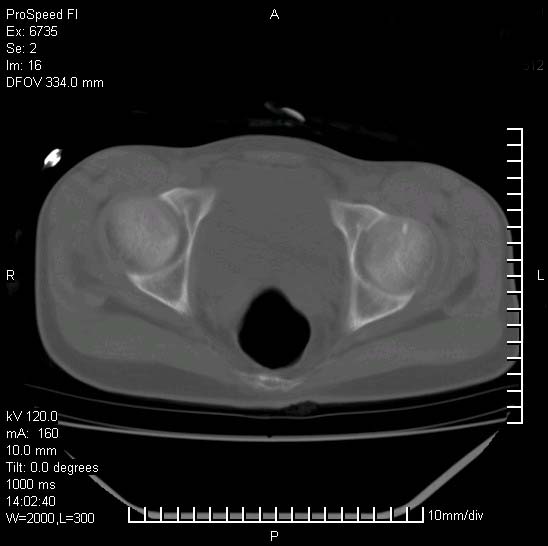

患者自诉胯部疼痛两年余,在当地服用中药,半月前至本院考虑骶髂关节结核,给予抗痨治疗。现发展至右下肢疼痛明显,活动受限,以膝关节处明显,拍膝关节平片无明显异常。

左侧骶髂关节面限局性骨破坏,边缘硬化关节腔见钙化物;不出外tb

右侧骶髂关节也有类似改变,只是较左侧轻,首先考虑强直性脊柱炎,不除外结核,建议作hla-b27检查。

典型强脊炎改变,髋关节亦有累及

符合强直性脊柱炎表现。